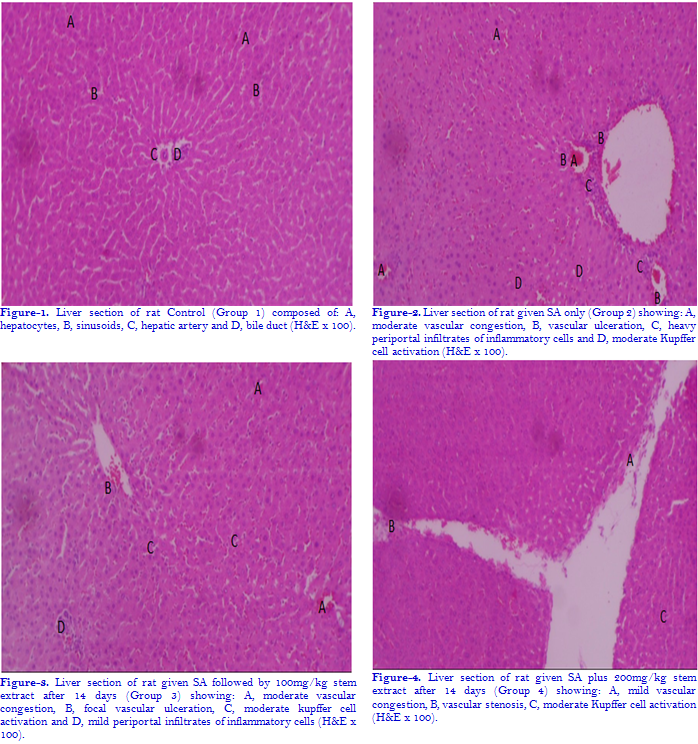

3.2. Effect of Ethanol Stem Bark Extract of Irvingia gabonensis O’Rorke Baill on Liver Histology of Experimental Rats in Presence or Absence of Sodium Arsenite Toxicity

Intoxication of the experimental animals with sodium arsenite (SA) for a period of 14 days  induced severe vascular ulceration, congestion perivascular infiltrates of inflammatory cells and Kupffer cell activation which are features of portal hepatitis in the liver. On administration of graded doses (100, 200, and 400mg/kgbw) of ethanol stem bark extract of Irvingia gabonensis O’Rorke Baill both simultaneously and after 14 days of SA exposure (post-treatment), there was mild amelioration of the hepatitis with the post-treatment and a better amelioration with the simultaneous administration. The results are shown in the photomicrographs.

Histopathological assessment of liver tissues showed that there were no visible lesions in the liver of the animals in the control group. In contrast, exposure to sodium arsenite alone produced vascular congestion and ulceration, infiltration of inflammatory cells and moderate Kupffer cell activation. On administration of graded doses of ethanol stem bark extract, 14 days later and simultaneously, there was mild amelioration of the hepatitis with the first modality and a better amelioration with the simultaneous treatment. This is consistent with findings from previous studies on the hepatotoxicity of sodium arsenite [74, 75].